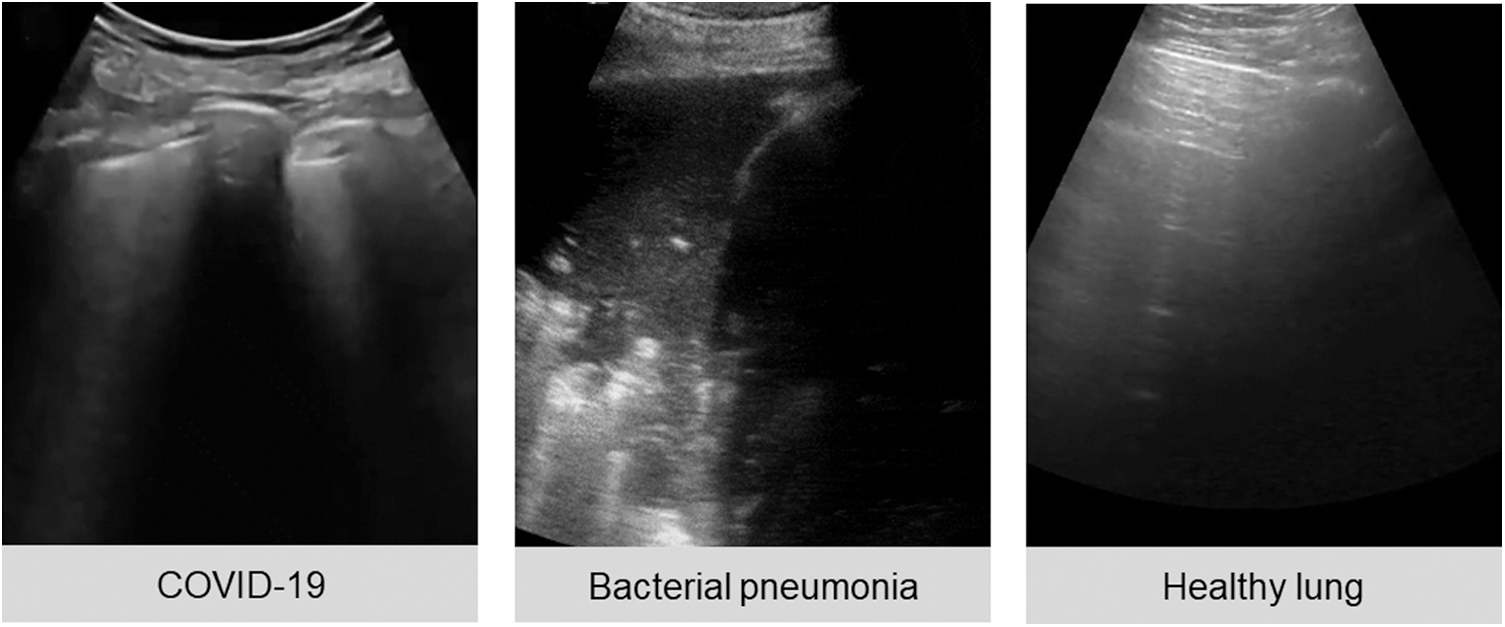

The public lung US POCUS database [3] has been used in this study. It consists of 911 images extracted from 47 videos of convex US probe scanning. This dataset includes three different classes of images: infectious COVID-19 (339 images), bacterial pneumonia (277 images), and the healthy lung (255 images), as presented in Fig. 1. Small subpleural consolidation and pleural irregularities can be shown for the positive case of COVID-19, while dynamic air bronchograms surrounded by alveolar consolidation are the main symptoms of bacterial pneumonia disease [3].

Figure 1: Three ultrasound images represent different cases of COVID-19, bacterial pneumonia, and healthy lung